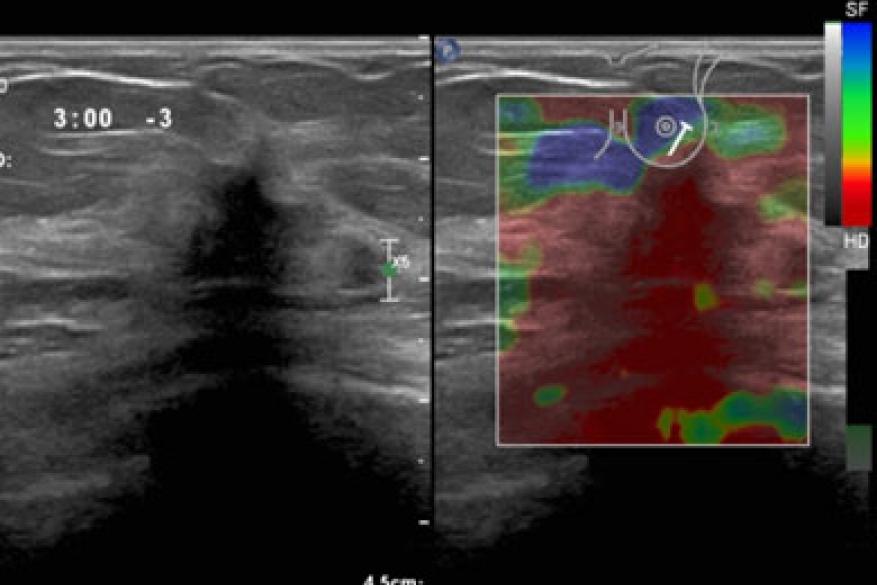

Η ελαστογραφία με υπερήχους μαστού είναι μια  υπερηχογραφική τεχνική απεικόνισης που παρέχει πληροφορίες για βλάβες του μαστού εκτός από το συμβατικό υπερηχογράφημα  και τη μαστογραφία.

Η ελαστογραφία διατμητικού κύματος(SWE) είναι μια νεότερη τεχνολογία υπερήχων που χρησιμοποιείται για τον έλεγχο της ακαμψίας των ιστών. Ένας μορφοτροπέας εκπέμπει παλμούς υψηλής έντασης που παράγουν κύματα διάτμησης, τα οποία δημιουργούν μια εικόνα υψηλότερης ποιότητας.

Η αξιολόγηση BIRADS βελτιώνεται από το SWE στη διαφοροποίηση των καλοήθων από κακοήθεις βλάβες του μαστού. Μια μέση τιμή  ελαστογραφίας (EMean) ≤ 72 kPa είναι εξαιρετικά ευαίσθητη και ειδική για τον χαρακτηρισμό καλοήθων βλαβών.

Οι καρκίνοι του μαστού είναι συνήθως ελάχιστα παραμορφώσιμοι σε σύγκριση με τις καλοήθεις βλάβες. Ωστόσο, ορισμένες καλοήθεις βλάβες μπορεί να είναι ελάχιστα παραμορφώσιμες: όπως το ινώδες ινοαδένωμα ή οι ουλές.

Η υπερηχογραφική ελαστογραφία έχει 86,5% ευαισθησία, 89,8% ειδικότητα και 88,3% διαγνωστική ακρίβεια στη διαφοροποίηση καλοήθων από κακοήθεις συμπαγείς μάζες μαστού.